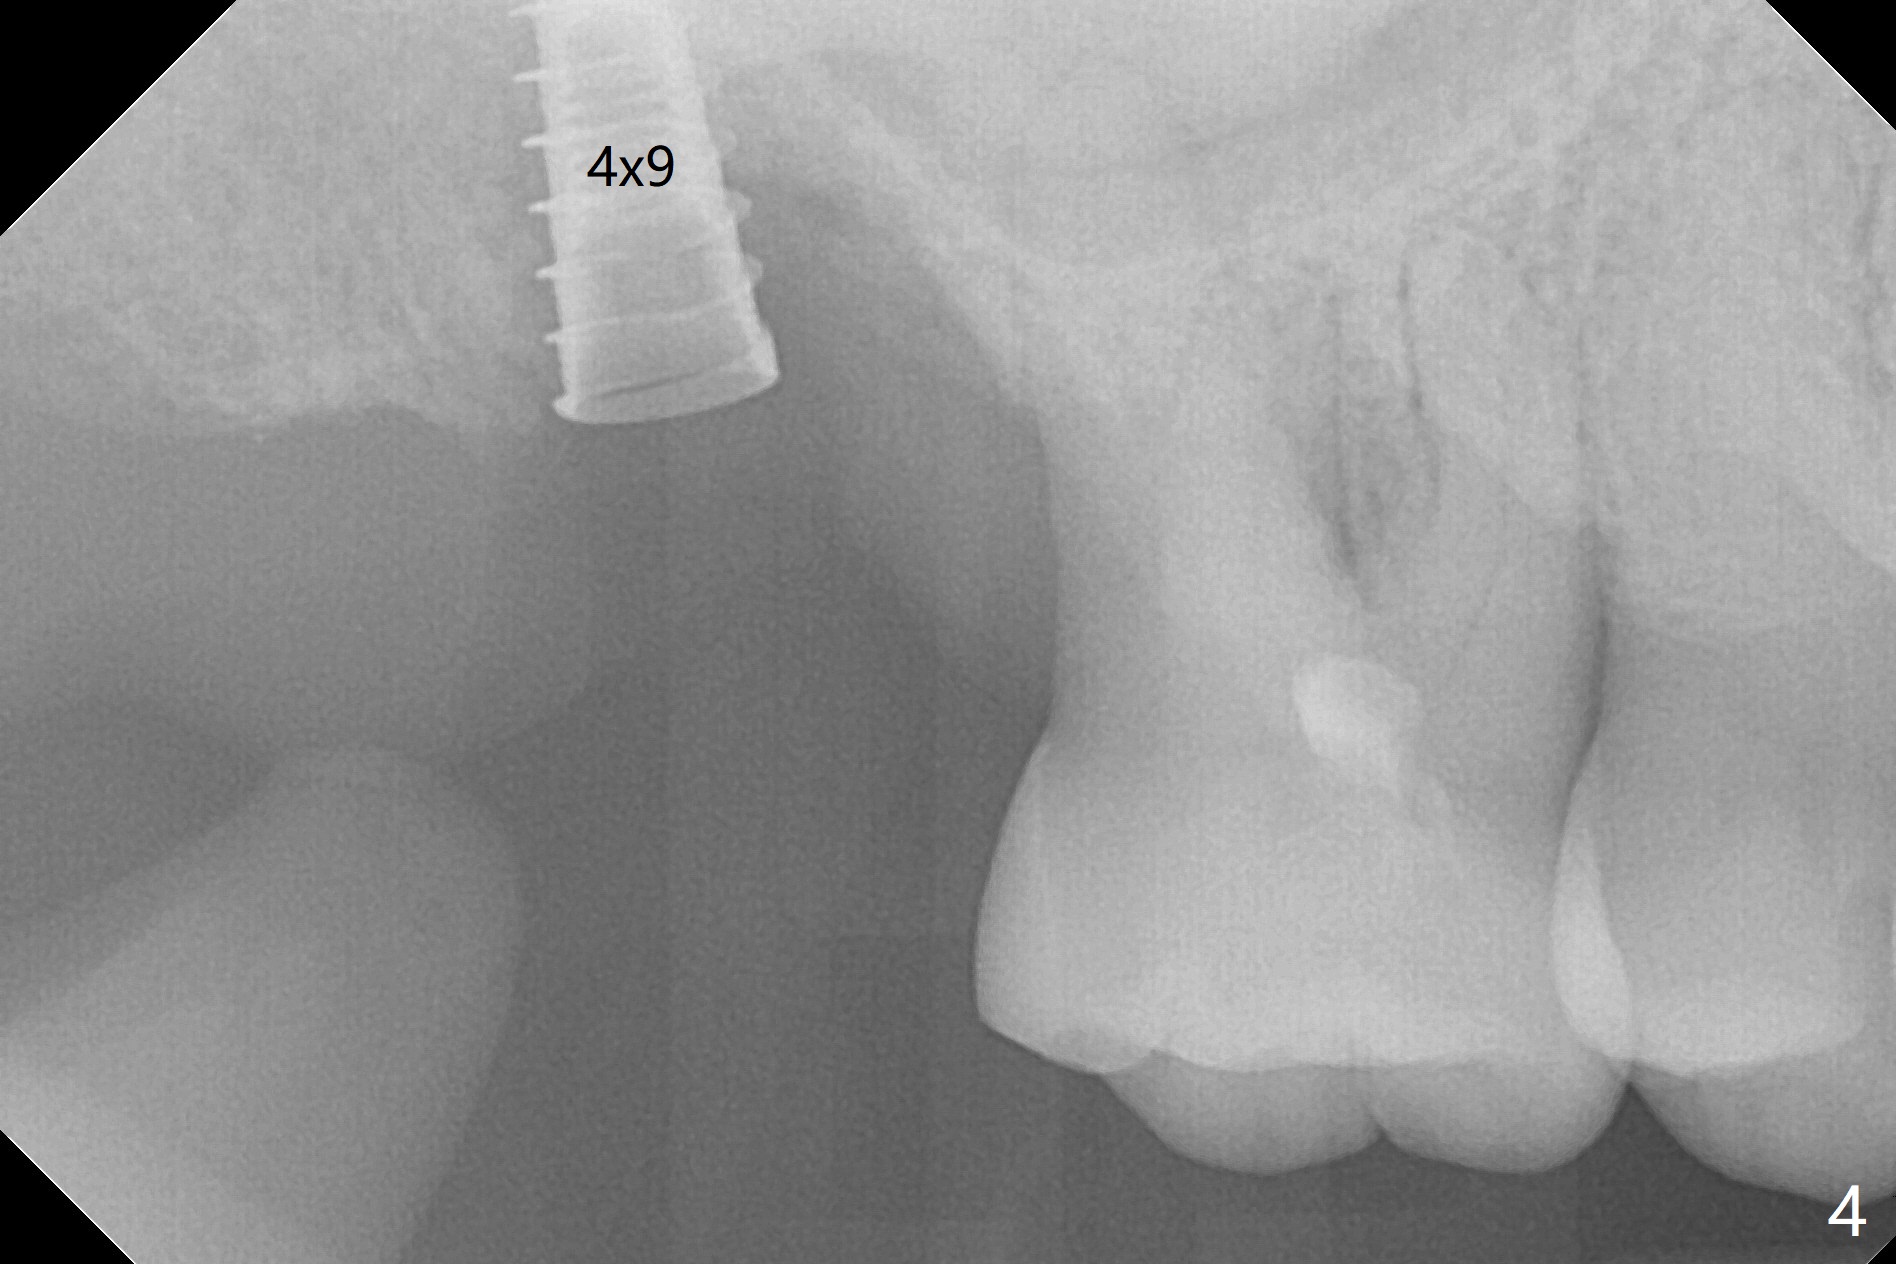

After extraction of the tooth #2 (Fig.1), osteotomy is supposed to be initiated in the mesial slope (Fig.2 arrow). With Magic Expanders (3-4.8 mm), osteotomy ends up in the bottom of the socket (Fig.3). Trajectory is found to be off when 4x9 and 5x9 mm dummy FC implants are placed with stability (Fig.4,5). The final implant, Magicore (5x7(3)mm, >29 Ncm), appears to be placed too deep for restoration (Fig.6,7); a screw retained crown may be a solution. PRF membrane and Vanilla (allograft) are used for sinus lift (no sinus membrane perforation). Following Vanilla graft in the socket gap (Fig.6 *), another piece of PRF membrane is used to cover socket opening. The membrane is fixed in place with suture and periodontal dressing. The implant seems to have osteointegrated 3.5 months postop (Fig.8). After change to 4.3x5 mm solid abutment and mesial surface adjustment, impression is taken for early loading because of removal of #14 implant. In fact the patient is satisfied with mastication improvement at #2 later on.